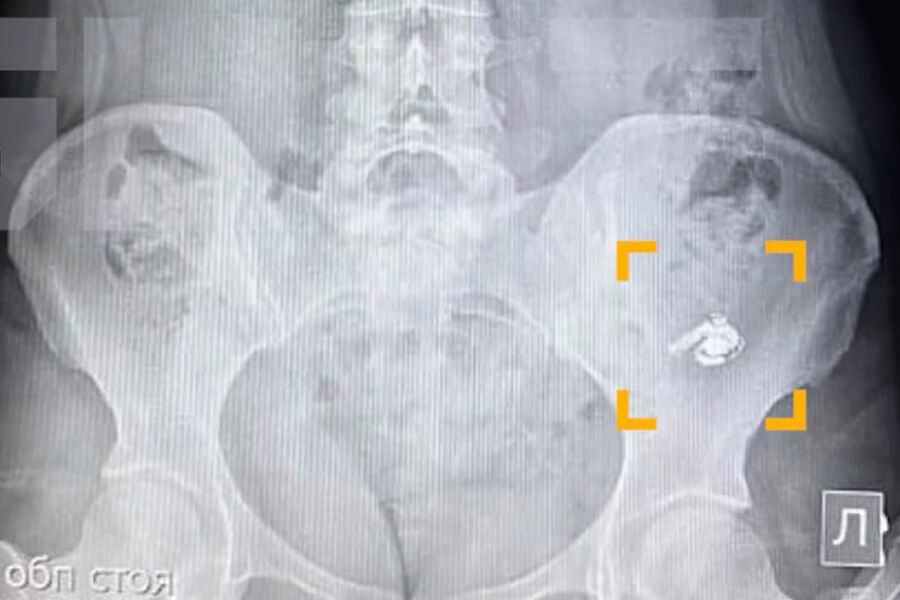

По словам уфимки по имени Мария, в момент глотания она почувствовала дискомфорт, но решила, что ей попалась крупная таблетка. Позже, обнаружив пропажу одного из наушников, девушка обратилась за медицинской помощью. В больнице ей сделали рентген, который подтвердил наличие инородного предмета в желудке.